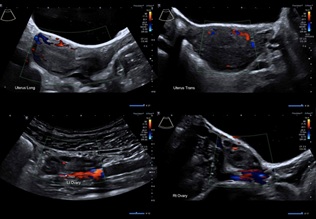

8:00am Systematic inspection of pelvis conducted. Uterus, ovaries and fallopian tubes appeared normal. Appendix, liver and sub-diaphragmatic surfaces also normal. Uterus was propped up by the assistant with forceps through the suprapubic port (Figure 6).

Figure 6: Before Bilateral Salpingo-Oophorectomy

8:10am Two gunpowder patches consistent with endometriosis identified on left pelvic side wall and in Pouch of Douglas (Figure 7). Both excised and sent for histopathology.

Figure 7: Endometriosis